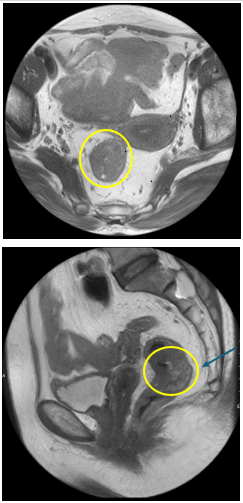

- MRI vùng tiểu khung :

Hình 3: Hình ảnh khối u trực tràng qua MRI cách rìa hậu môn 55mm, ngang mức bờ dưới S3 và xương cụt, dài 35mm, dày nhất 15mm.

+ T : Xâm lấn đến lớp cơ, chưa rõ thâm nhiễm mỡ ra ngoài khoang mỡ xung quanh trực tràng. Tương ứng T2/3a

+ N: Tương ứng N1

- Số hạch mạc treo trực tràng nghi ngờ ác tính :1

- Số hạch chậu trong nghi ngờ ác tính : 0

- Số hạch khoang bịt nghi ngờ ác tính : 0

+ MRF (-)

+ EMVI (-)